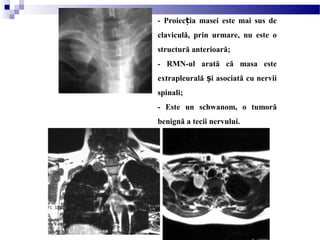

- Proiec ia masei este mai sus deț

claviculă, prin urmare, nu este o

structură anterioară;

- RMN-ul arată că masa este

extrapleurală i asociată cu nerviiș

spinali;

- Este un schwanom, o tumoră

benignă a tecii nervului.